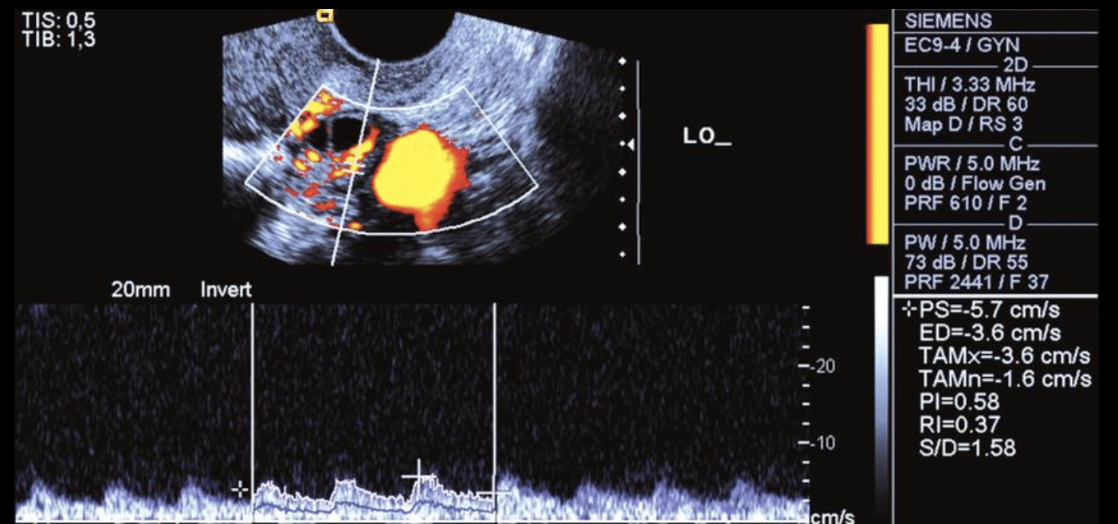

¿Onda anormal o trifásica?

Anormal

*Imagen arriba es normal, abajo es anormal

¿Cómo se mide el reflujo venoso?

Se le pide al paciente que haga valsalva y en el doppler se invierte el flujo